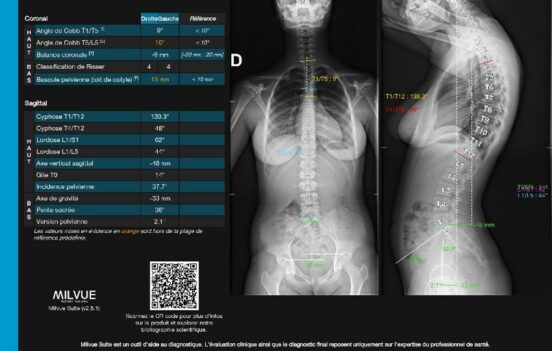

TechCare Metrics est le module de la Milvue Suite qui propose une analyse détaillée des bilans orthopédiques grâce à l’automatisation de certaines mesures utiles en imagerie ostéo-articulaire. Pour les patients, c’est la garantie d’un diagnostic et d’un suivi de qualité supérieure.

Les mesures sont compatibles EOS, avec rapport d’analyse.

SORTIES INTUITIVES montrant les vues de face et de profil ensemble.